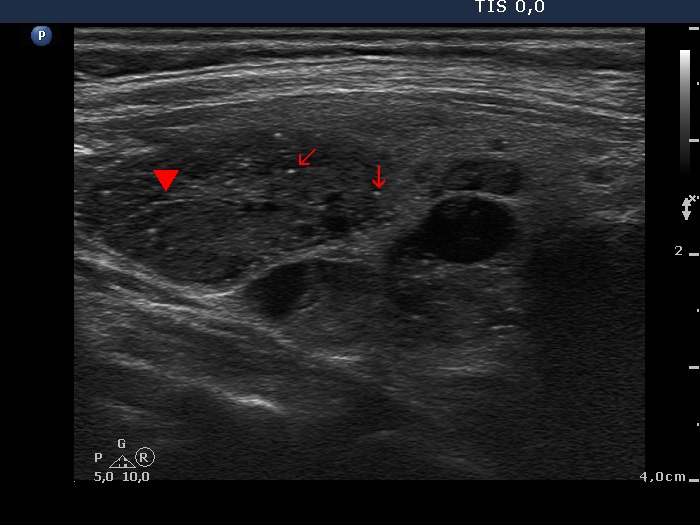

Benign hyperplastic nodule (histological diagnosis) - case cons037 |

Upper part of the right lobe |

|

The bright hyperechogenic granules (arrows) seem to be at first sight punctate echogenic foci. However, the presence of a few hyperechogenic lines (arrowheads) challenges this view: these figures might be presentations of a connective tissue.